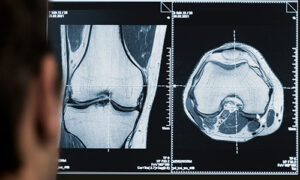

Curso de imágenes para todo el equipo de salud

Sociedad Argentina de Radiología y Federación Argentina de Radiología